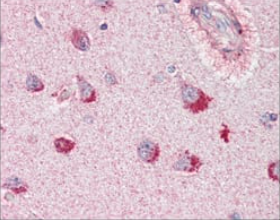

SORL1 Mouse Monoclonal antibody[3B6B11]

SORL1 (sortilin-related receptor, L A repeats containing) also known as sorting protein-related receptor containing LDLR class A (SorLA), is a Type I membrane protein that may be involved in cell-cell interaction. SorLA, a single transmembrane receptor, binds LDL and transports it into cells by endocytosis. SorLA is synthesized as a proreceptor which is processed to the mature form by a furin-like propeptidase. It can also bind to RAP (receptor-associated protein). SorLA is a multifunctional endocytis receptor important in lipoprotein and protease uptake. The N-terminal propeptide, which is removed, can be cleaved by furin or homologous proteases. Endogenous SorLA binds the neuropeptide head activator (HA) and is important for HA signaling and function. The gene encoding for the protein maps to chromosome 8p23.1. SorLA is expressed mainly in brain (cerebral cortex, cerebellum and the occipital pole), but can also be found in liver, spinal cord, kidney, testis and pancreas.

IHC    1/200 - 1/1000